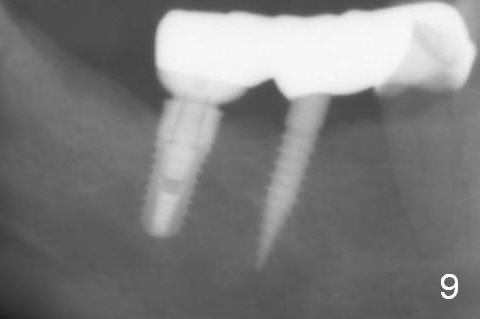

Bone loss around the implants remains minimal 7 months post cementation (10 months postop, Fig.9).